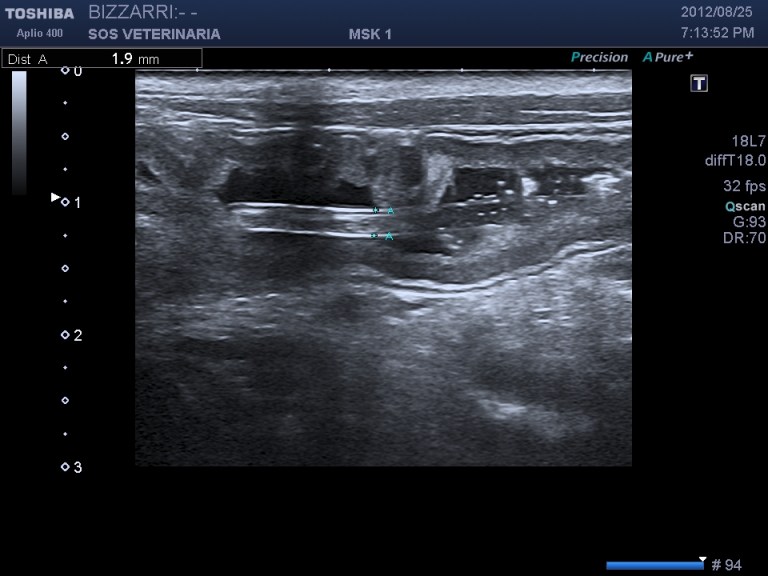

ascaride all’interno del lume diametro inferiore ai 2mm,non si evidenzia cono d’ombra

L’ascaride si differenzia ecograficamente dal copo estraneo filiforme per la presenza della parete esterna (cuticola) ,una parte interna parenchimale e l’assenza di cono d’ombra ,inoltre l’intestino puo’ essere spastico ma mai circonvoluto con pattern a fisarmonica.